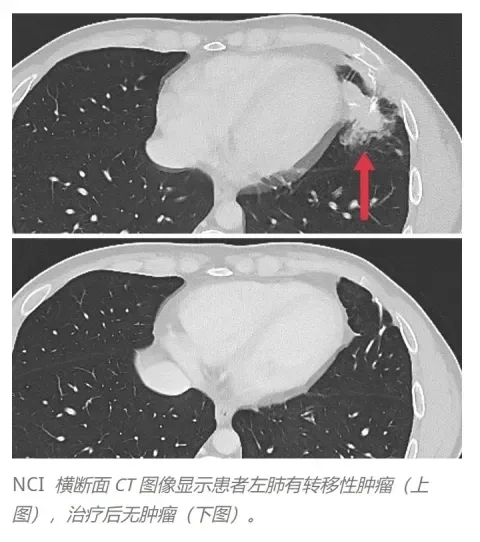

结果显示:按RECIST标准评估,3例患者出现客观临床反应,肝脏、肺及淋巴结的转移性肿瘤均消退,缓解持续4~7个月。

下图为一例典型患者接受TCR-T治疗前后左肺转移灶的CT图像对比:治疗前,患者左肺存在转移性肿瘤;治疗后,转移灶明显消退(详见下图)。